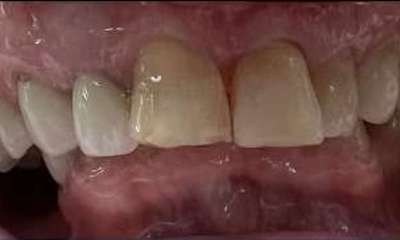

Crowns placed on front teeth to fix worn edges and darkening color of teeth. Crowns created harmony amongst the front teeth and gave the patient a more youthful smile.